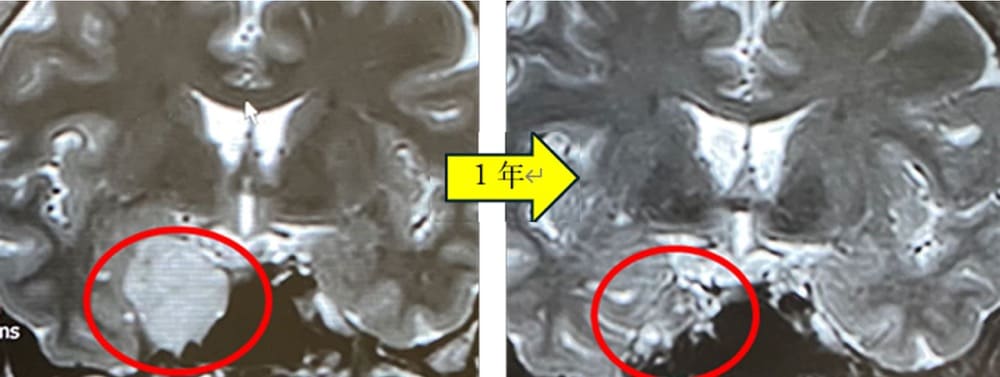

海綿静脈洞内腫瘍(血管腫)症例ガンマナイフ後経過